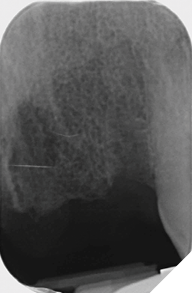

Radiographic examination shows the upper left lateral incisor tooth has decayed through and through and the upper right central incisor tooth is heavily root treated and filled (Figs. 1-2).

Fig. 1

Fig. 2